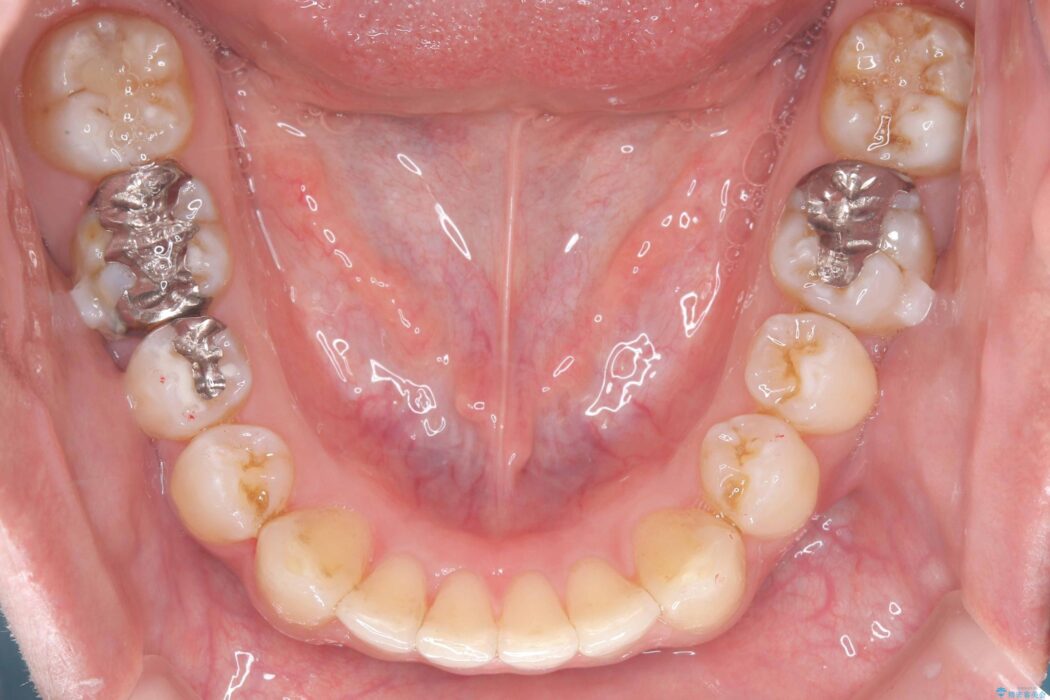

歯の隙間とデコボコ、シザーズバイトも改善され、咬み合わせや見た目が整い、患者様にも大変ご満足いただけました。